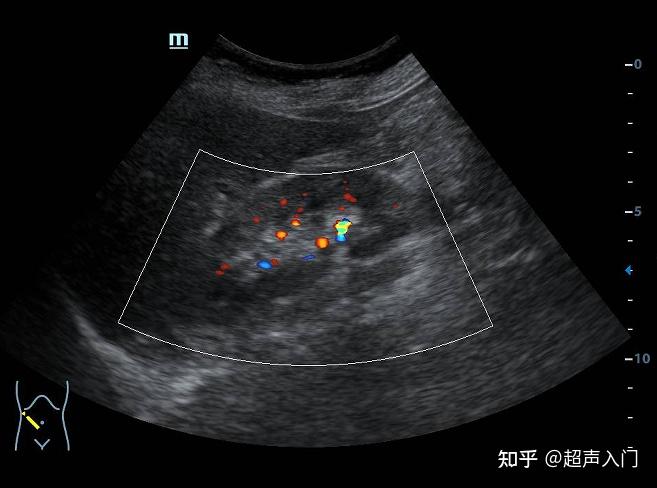

超声 #超声影像 #肾结石 找输尿管结石也需要优化机器参 - 兑趑

肾结石超声诊断及鉴别